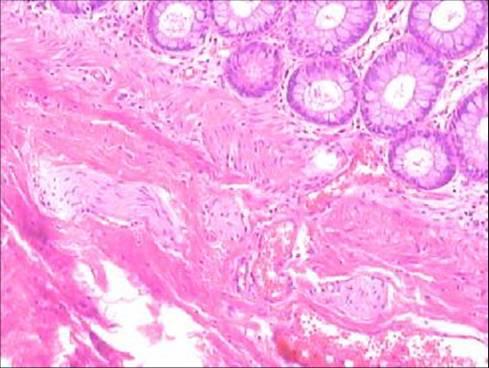

潰瘍性結(jié)腸炎的治療方法

潰瘍性結(jié)腸炎的病因至今仍不明?;蛞蛩乜赡芫哂幸欢ǖ匚?。心理因素在疾病惡化中具有重要地位,原來(lái)存在的病態(tài)精神如抑郁或社會(huì)距離在結(jié)腸切除術(shù)后明顯改善。有認(rèn)為潰瘍性結(jié)腸炎是一種自身免疫性疾病。

目前認(rèn)為炎性腸病的發(fā)病是外源物質(zhì)引起宿主反應(yīng)、基因和免疫影響三者相互作用的結(jié)果。根據(jù)這一見解,潰瘍性結(jié)腸炎與克隆病是一個(gè)疾病過(guò)程的不同表現(xiàn)。